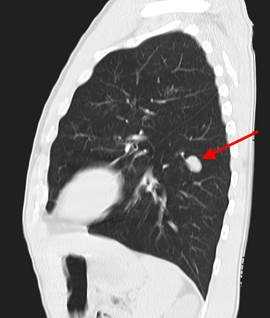

Метастазы в легких на КТ

Гематогенные метастатические узлы в легких на КТ имеют довольно четко очерченные и ровные контуры. Нечеткие, расплывчатые или лучистые контуры наблюдаются в том случае, если есть инвазивный рост в окружающую легочную ткань. Локализуются преимущественно в нижних, периферических отделах легких, хаотично, без очевидной связи с бронхами и крупными легочными сосудами.

Вторичные узлы гематогенного характера чаще всего имеют ровные края, четкие контуры и однородную структуру. Возможны изменения структуры опухоли вследствие кровоизлияния в паренхиму, обызвествлений, некроза центральной части узла, а также рубцов. Края узла могут стать нечеткими, расплывчатыми, если опухоль провоцирует отек легочной паренхимы, либо «лучистыми», если имеет место опухолевый лимфангиит.

Чаще всего метастазы выглядят как множественные очаги. Одиночные вторичные узлы крайне редки и встречаются меньше чем в 5% случаев. Чем больше узлов выявлено, тем выше вероятность их метастатической природы. Одиночный метастаз нужно дифференцировать с первичным раком, для этого обычно требуется тканевое исследование после оперативного вмешательства или биопсии.

Гематогенные метастазы наиболее часто локализуются в периферических отделах легких, вдали от крупных сосудисто-бронхиальных пучков, вблизи плевральной оболочки. При множественных поражениях гематогенного характера наблюдается тенденция к увеличению количества очагов в направлении «сверху-вниз». Чаще гематогенные метастазы расположены хаотично, вне четкой связи с бронхами и видимыми легочными сосудами. Практически не бывает такого, чтобы гематогенные вторичные узлы находились только с одной стороны, или занимали только одну долю или сегмент. При наличии такого распределения в первую очередь нужно думать о туберкулезе (верхние доли), множественных абсцессах и т. д.